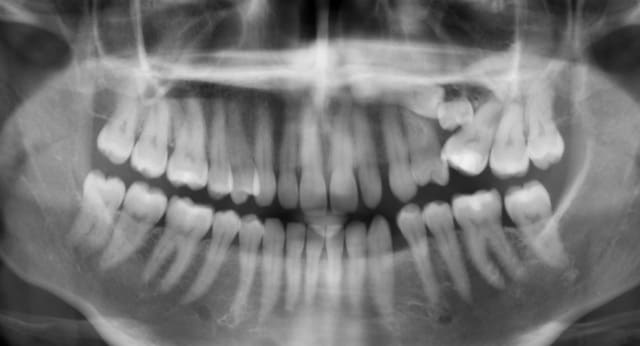

le panoramique est claire.. embouteillage entre 25, 26 et 65.

que proposez vous pour régler cette situation??

extraction 26 +65 et c'est tout?

extraction 26 65 et 25

25 est en palatin ou vestib? Seule la cbct peut donner une idée de la stratégie, amha.

Si le patient se lance dans l'odf aucune raison de virer la 26.

Extraire 65 dans tout les cas et 25 suivant ce que dit le CBCT.

Mon traitement idéal serait virer la 65, voir pour virer la 25. Multiattaches pour réorganiser le secteur antérieur et amener la 26 à sa place. Ce qui libérera l'espace pour un implant en place de 25.. Elle passe son cbct lundi.

Virer la 65, refermer les espaces en anterieur haut et bas ce qui permet d amener la 26 contre 24?